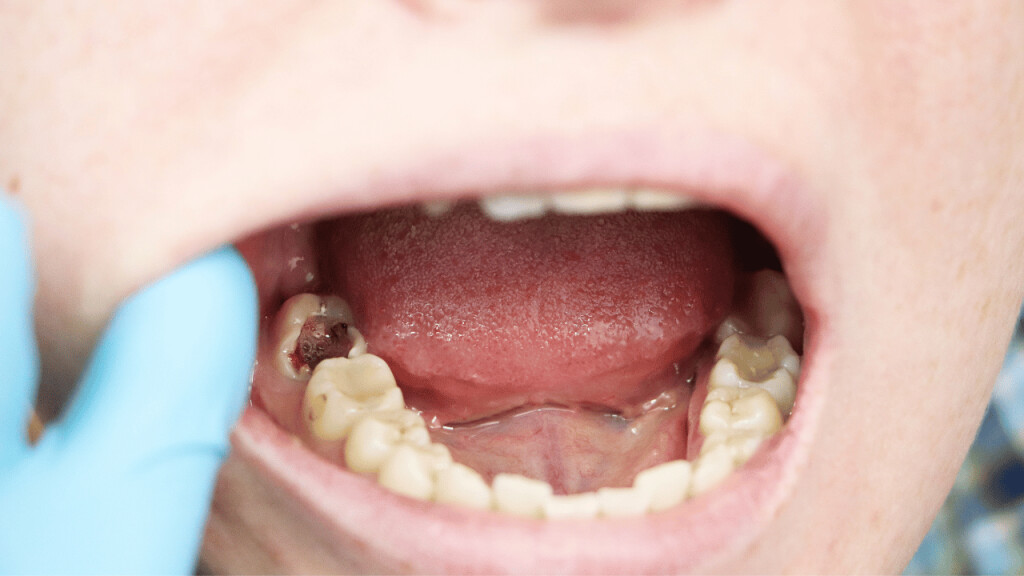

A loose tooth can be very annoying and discomforting. Your oral hygiene, gum disease, teeth grinding, hard food, mouth injury, anything can result in a loose tooth. You can let your tooth come out on its own. But the issues that come with that, like problems in eating food, constant sensitivity, etc can be hard to bear. And you just can’t keep waiting for your tooth to fall on its own for a long time. So, how to get a tooth out in a fast and painless way?

How to pull an adult tooth out without pain?

There are a few ways through which you can pull out a loose tooth without hurting yourself. However, if you are experiencing any kind of inflammation or pain, it is advisable that you visit a dentist.

These are a few ways to get a tooth out in fast and painless ways. But the process doesn’t stop here. Aftercare of your gum is very important.

Aftercare tips after pulling out a tooth

Pulling out a tooth can be quite painful and finding a little blood on the spot is common. Here are a few care tips after pulling out the loose tooth.

1. Use sterile gauze

Apply a little pressure on the tooth socket using sterile gauze to stop the bleeding. The bleeding should stop in a few minutes. You can also press it gently using the upper tooth.

4. Wait for 24 hours before rinsing

After pulling the tooth, there will be a blood clot in the tooth socket. This clot will help the area to heal properly hence it is vital to let it remain in place for 24 hours at least. So, wait for that time before rinsing your mouth. Use a straw to drink water and avoid anything that can result in suction or vigorous rinsing.

If you are still feeling pain or sensitivity even after two-three days of pulling the tooth out, visit your dentist.

Try not to pull out your loose tooth until it is absolutely necessary. In case of any discomfort, pain, swelling in gums, and inflammation, visit your dentist immediately.